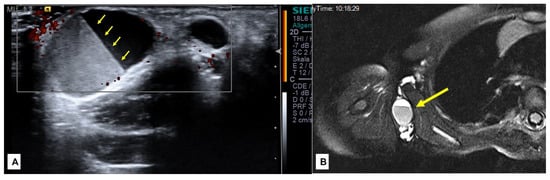

While SGA patients regularly presented with a firm, nontender lump persisting for at least one month, patients with SVM presented with various medical histories and clinical presentations. Twenty-two patients with SVM (47%) presented at their first encounter between birth and the third year of life. Only four (18%) of these patients had a sudden enlargement of the affected area of the body, which was caused by intracystic bleeding (Figure 5). Parents were aware of their child’s vascular malformation from birth or the first month of their life in 15 cases (68%). Eight patients (17%) presented between their fourth and 10th year of life. Among them, five (63%) patients had a sudden enlargement of the lesions with intracystic bleeding.

Figure 5.

A 2.5-year-old girl with a sudden appearance of a lump in the right axilla. Ultrasound examination showed a multi-cystic mass with intracystic bleeding documented by the fluid-fluid level in the cyst representing the clot retraction (A)—(yellow arrows). The MRI (B) showed the exact extension of the mass (arrow), which was limited to the subcutaneous tissue and facilitated the indication for surgical resection.